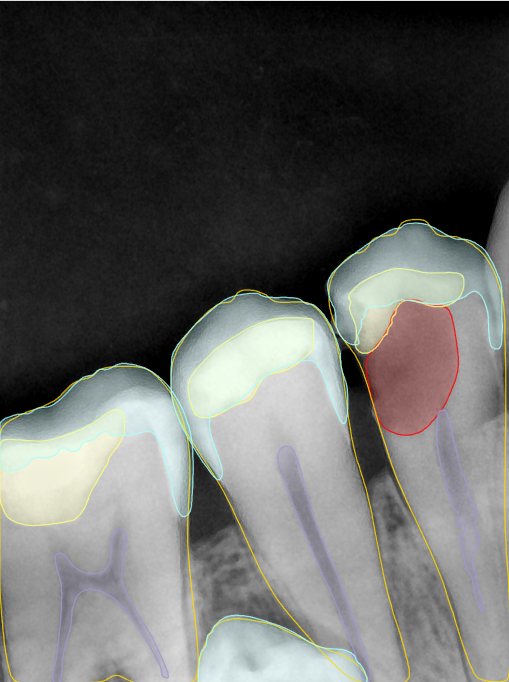

第二版算法问题测试

| 第一版 | 第二版 | 是否解决 | |

|---|---|---|---|

![]() | ![]() ![]() 边角识别有问题 龋齿识别不全 牙髓识别不全 | ![]() | 解决 |

![]() | ![]() 边角识别有问题 识别信息有误 自查(牙冠识别不全) | ![]() | 解决 |

![]() | ![]() ![]() 边角识别有误 大范围填充识别遗漏 | ![]() | 解决 |

![]() | ![]() 识别信息不全 | ![]() | 解决 |

![]() | ![]() ![]() 边角问题 牙胶识别不全 牙冠识别不全 | ![]() | 解决 |

![]() 换图片 | ![]() | ![]() 牙冠部分稍微白了一些就识别成小范围修补,部分判断异常 | 部分解决,修复类略敏感,牙冠部分稍微白了一些就识别成小范围修补,部分判断异常。 |

![]() | ![]() ![]() 牙冠识别不全 牙髓不全 根尖炎龋齿识别有误 | ![]() | 解决 |

![]() | ![]() | ![]() | 解决 |

![]() 换图片 | ![]() | ![]() | 解决 |

![]() | ![]() 牙冠识别有误 | ![]() | 解决 |

![]() 换图片 | ![]() ![]() 边角识别有误 | ![]() 修复类敏感 | 部分解决,图像过白,导致修复类判断异常。 |

![]() 换图片 | ![]() 牙冠识别不全 | ![]() 修复类敏感 | 部分解决,图像过白,导致修复类判断异常 |

结论:修复类出现了不鲁棒的情况,后续需要加入轮廓的扩充数据进行增强。